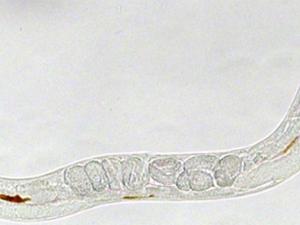

Descubren una nueva diana terapéutica para tratar la metástasis en el cáncer

La metástasis tumoral es responsable de más del 90% de las muertes por cáncer. De ahí el esfuerzo de los científicos por desarrollar nuevos tratamientos que contribuyan a frenar esta elevada mortalidad. Un equipo del <a href="https://www.csic.es/es" title="Consejo Superior de Investigaciones Científicas" alt="Consejo Superior de Investigaciones Científicas" target="_blank">Consejo Superior de Investigaciones Científicas</a> (CSIC) ha identificado una nueva diana terapéutica en las células tumorales metastáticas de cáncer colorrectal, melanoma y otros tumores, como cáncer de mama o pancreas. El trabajo, que se publica en la revista <a href="https://onlinelibrary.wiley.com/doi/abs/10.1111/pbi.12837?systemMessage=Wiley+Online+Library+will+be+unavailable+on+Saturday+7th+Oct+from+03.00+EDT+%2F+08%3A00+BST+%2F+12%3A30+IST+%2F+15.00+SGT+to+08.00+EDT+%2F+13.00+BST+%2F+17%3A30+IST+%2F+20.00+SGT+and+Sunday+8th+Oct+from+03.00+EDT+%2F+08%3A00+BST+%2F+12%3A30+IST+%2F+15.00+SGT+to+06.00+EDT+%2F+11.00+BST+%2F+15%3A30+IST+%2F+18.00+SGT+for+essential+maintenance.+Apologies+for+the+inconvenience+caused+." title="Clinical Cancer Research" alt="Clinical Cancer Research" target="_blank">Clinical Cancer Research</a>, de la <a href="https://www.aacr.org/Pages/Home.aspx" title="American Association for Cancer Research" alt="American Association for Cancer Research" target="_blank">American Association for Cancer Research</a>, constituye “un importante primer paso” según los autores.